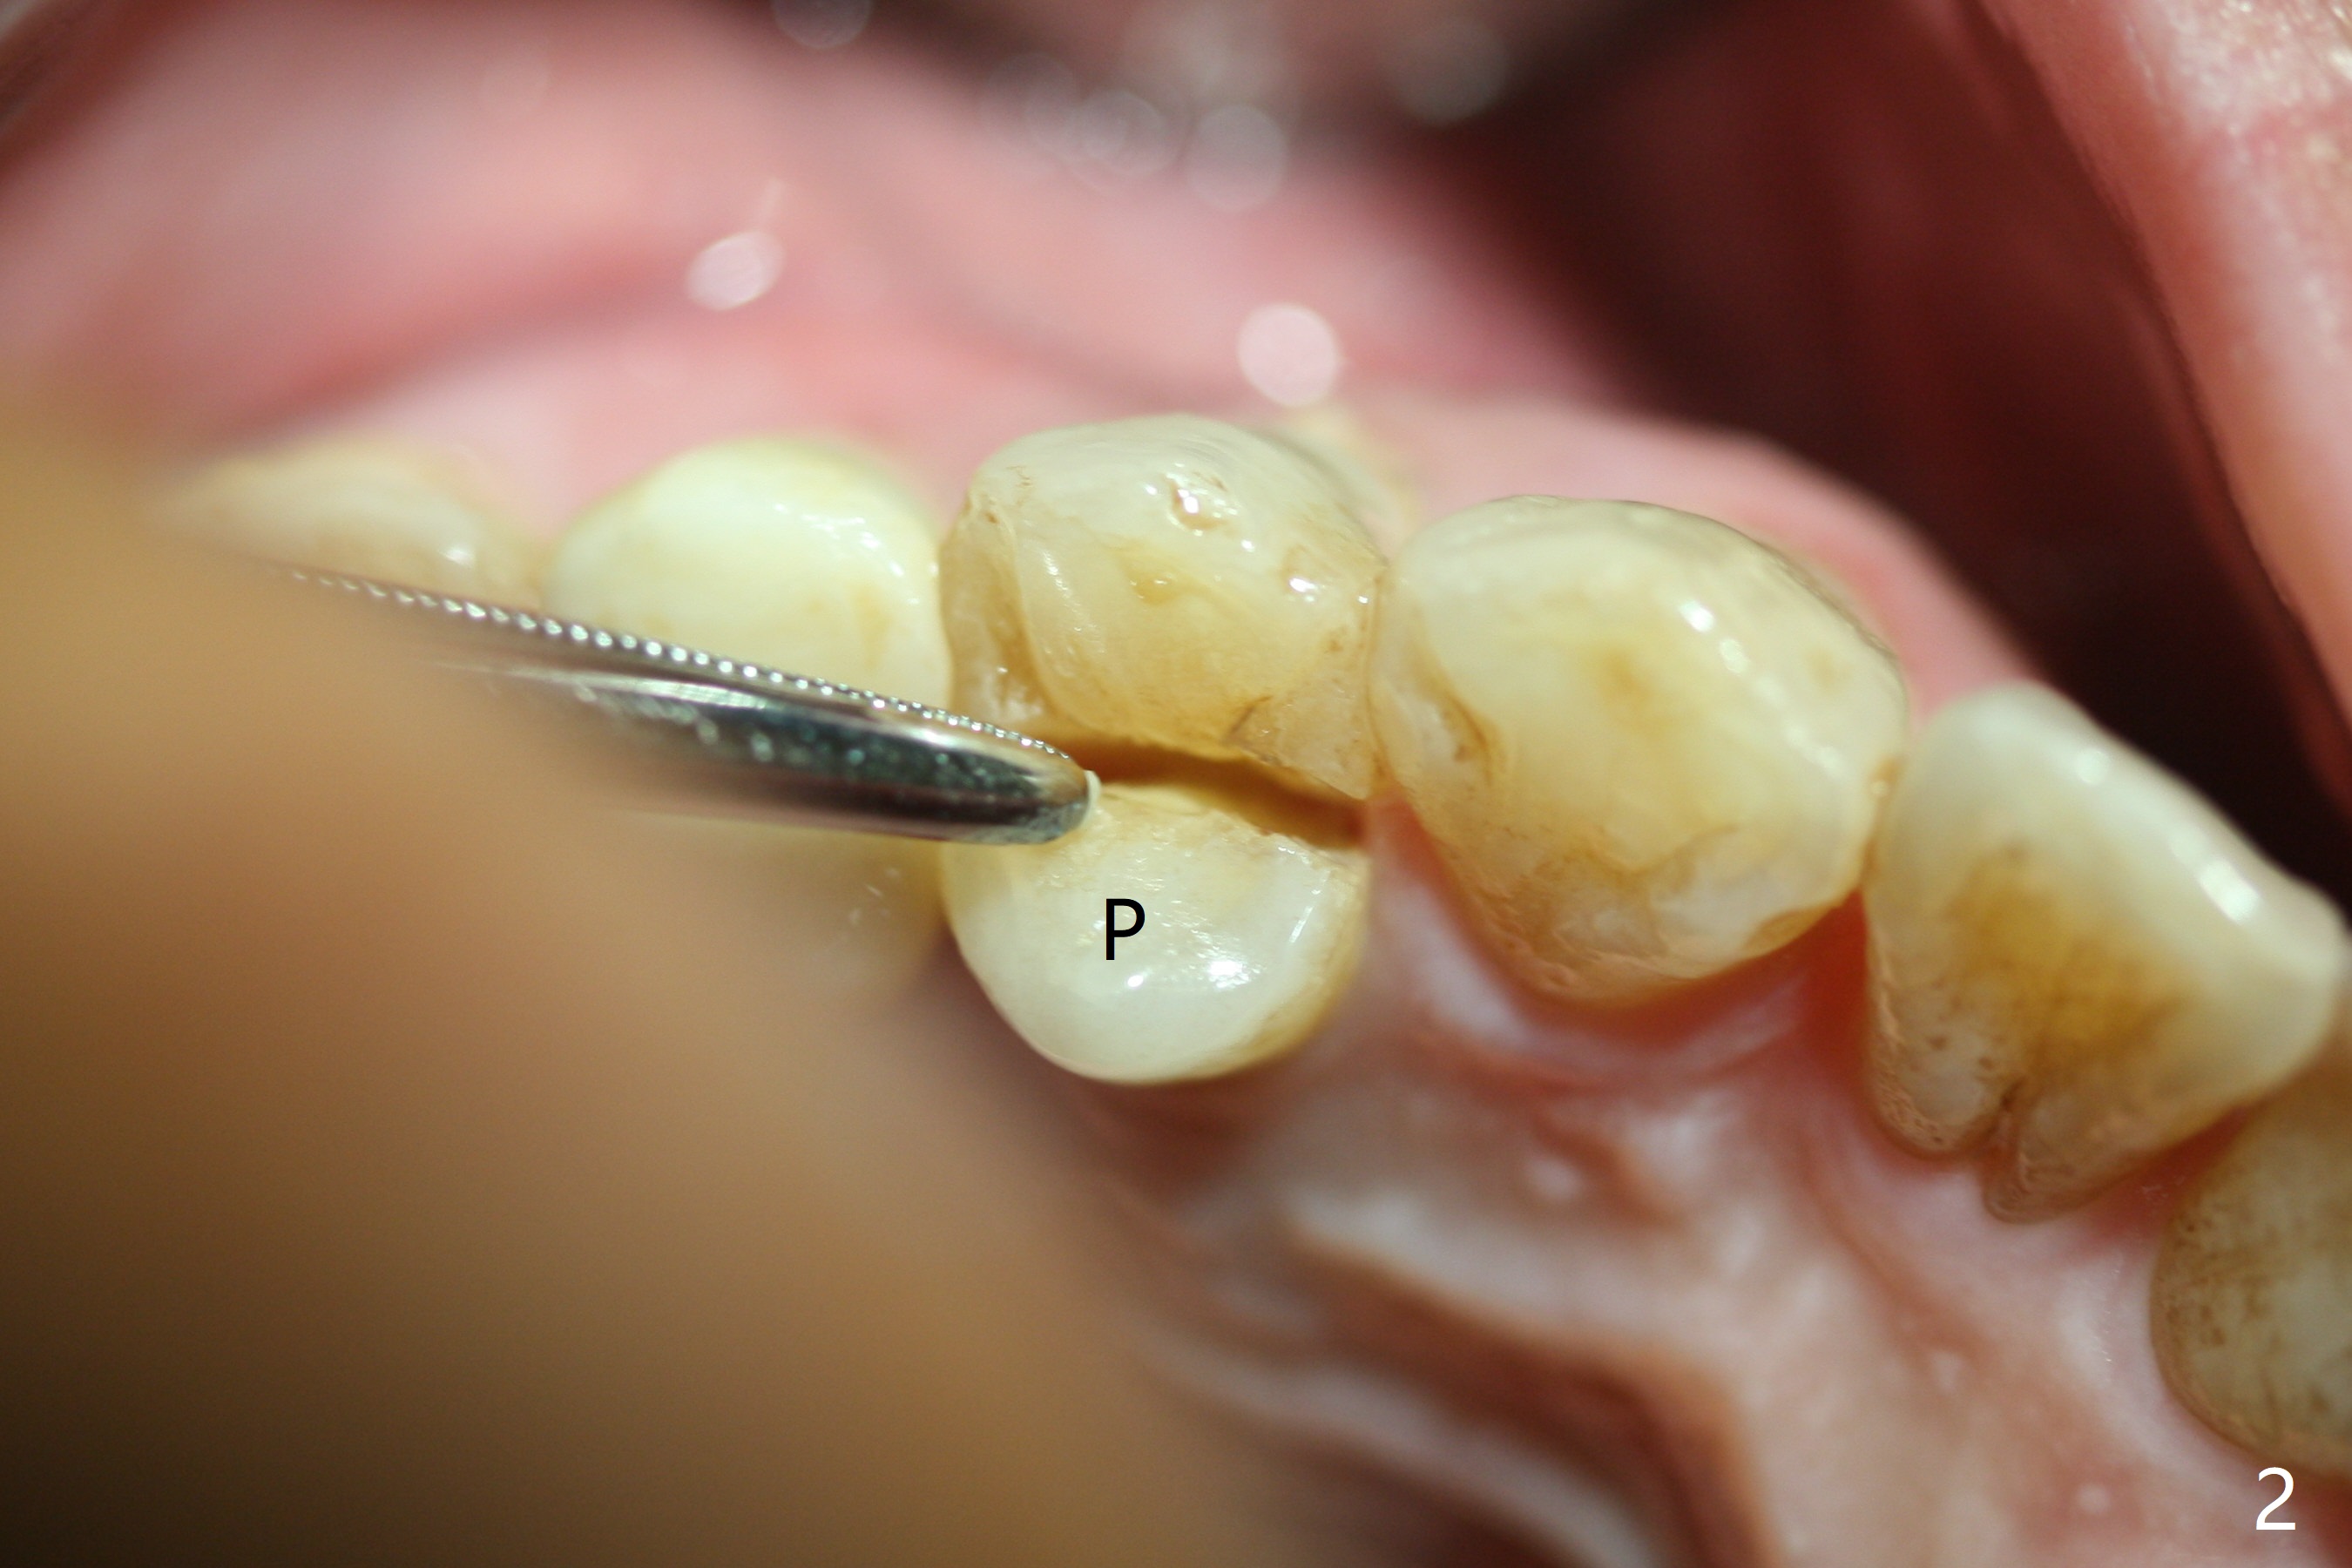

The buccal plate is normal at the tooth #5 (Fig.1) with the loose palatal fragment (Fig.2 P). Extraction leads to root fracture. Sectioning removes the palatal portion of the root and keeps the buccal semilunar piece (Fig.3 *); the mesiopalatal plate is resorbed (P). Initial osteotomy is off (Fig.4 (R: remaining root)). Redirection improves the trajectory (Fig.5). With the 2nd redirection (Fig.6 (4.5 mm tap)), a 4.5x12 mm implant is placed with 50 Ncm and sinus lift (Fig.7 black *); bone graft is placed with emphasis on the palatal defect (white *). As usual, an immediate provisional is fabricated. In fact the abutment may be not completely seated because of contact with the mesial crest. Prepare anesthetic and 5.5 mm profile drill. Take parallel BW or PA. Take occlusal photos to show no buccal or mesiopalatal atrophy. After 5.5 mm profile drill 11 months postop, the abutment has no contact with the mesial crest (Fig.8 <). Since the proximal contact between #3 and 4 is light with food impaction, the provisional at #5 is fabricated with tight distal contact. When the patient returns for final crown cementation (Fig.9), the food impaction is minimal between #3 and 4. The distal black triangle (Fig.10 *) and exposure of the abutment margin (^) are partially related to provisional fabrication and should dissolve over time considering socket shield.